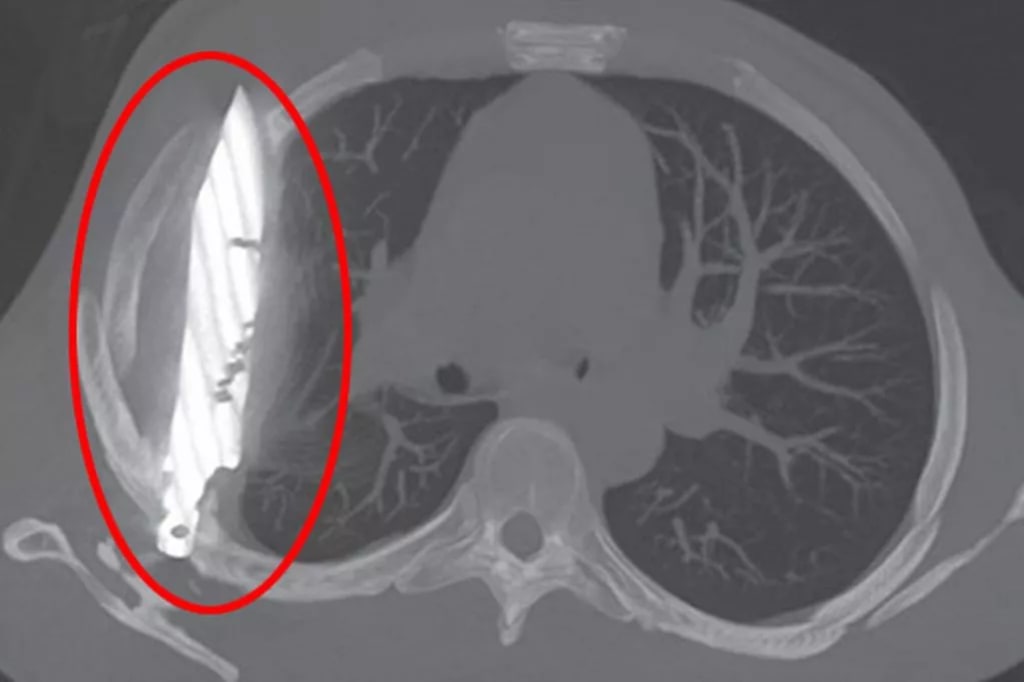

Initially baffled, doctors ran a series of diagnostic tests, including a chest radiograph (X-ray). The results stunned the medical team—there was a large knife blade lodged in the mid-thorax, perilously close to major organs.

The key lies in the placement of the blade. According to the surgical team, the knife:

Entered through the right scapula (shoulder blade)

Missed major organs, arteries, and the heart

Remained lodged in a way that caused minimal disturbance to surrounding tissues